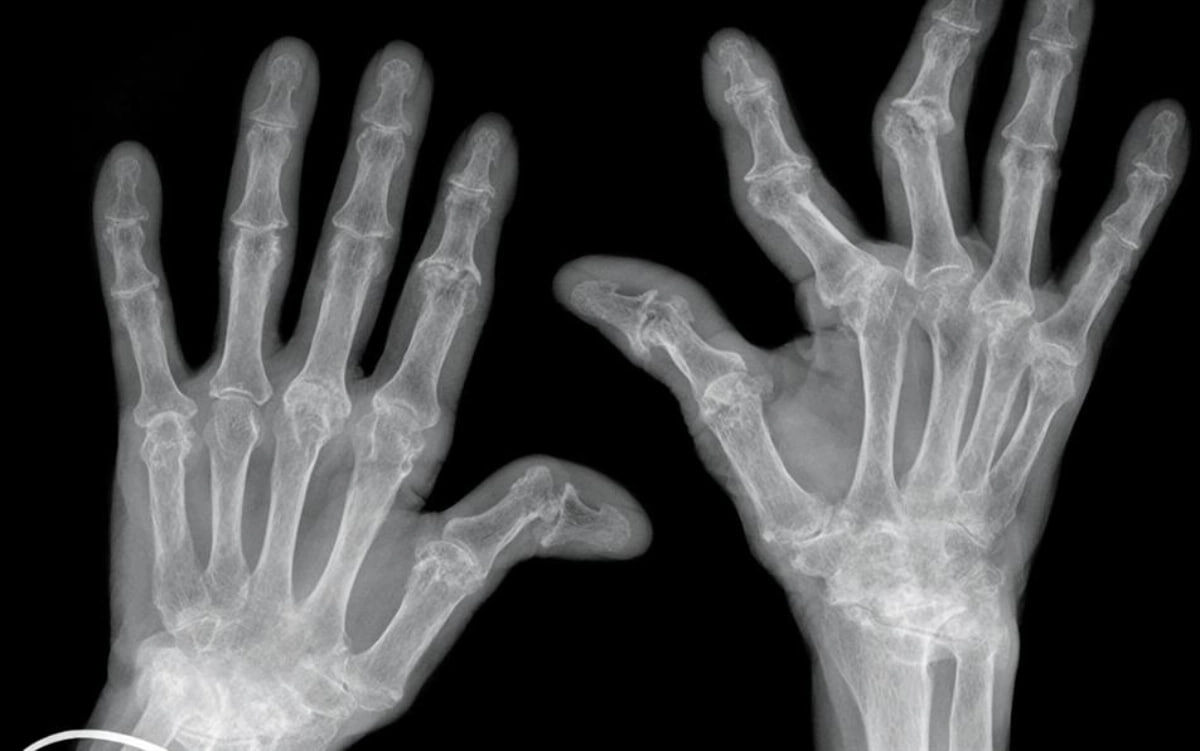

Новая технология выявляет артрит за 10 минут Ученые из Южной Кореи представили точную и быструю диагностику, которая не только выявляет артрит, но и определяет тип заболевания и степень прогрессирования. Сегодня пациентам необходимо пройти несколько этапов обследования, чтобы установить диагноз. Теперь для этого необходим только один прием у врача. https://hightech.plus/2025/04/28/novaya-tehnologiya-viyavlyaet-artrit-za-10-minut

Ученые из Южной Кореи представили точную и быструю диагностику, которая не только выявляет артрит, но и определяет тип заболевания и степень прогрессирования. Сегодня пациентам необходимо пройти несколько этапов обследования, чтобы установить диагноз. Теперь для этого необходим только один прием у врача.